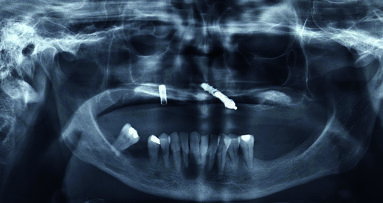

Lo scopo di questo articolo è presentare una alternativa terapeutica al rialzo di seno mascellare nei casi in cui si verifichi una estesa pneumatizzazione dei seni mascellari nella zona del primo premolare.

Questo caso clinico ha richiesto un inserimento ottimale di impianti sulla base di un piano di trattamento protesicamente guidato e di chirurgia guidata. ...

Nelle riabilitazioni implanto-protesiche del mascellare atrofico esistono delle alternative alla chirurgia di elevazione del seno mascellare che devono ...